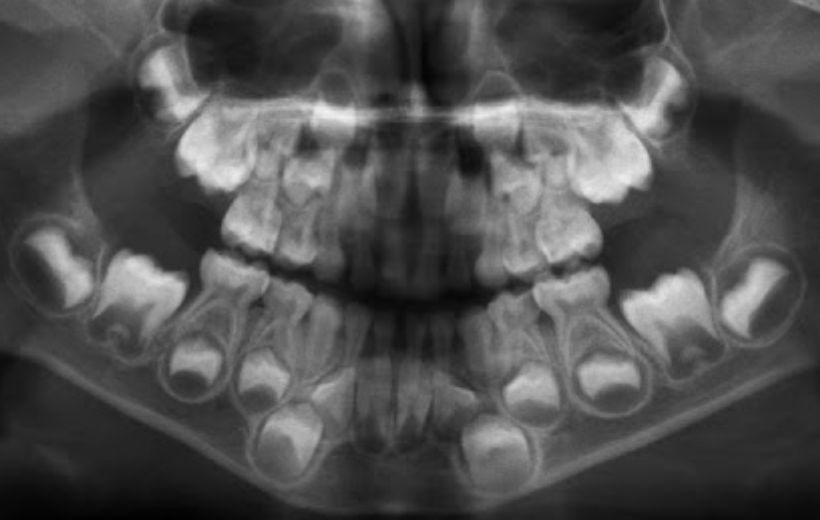

Permanent lower incisors present? Yes, so definitely 6-7

Permanent upper Incisors not erupted yet. Therefore not 7-8 y.o.

Conclusion = 6 y.o